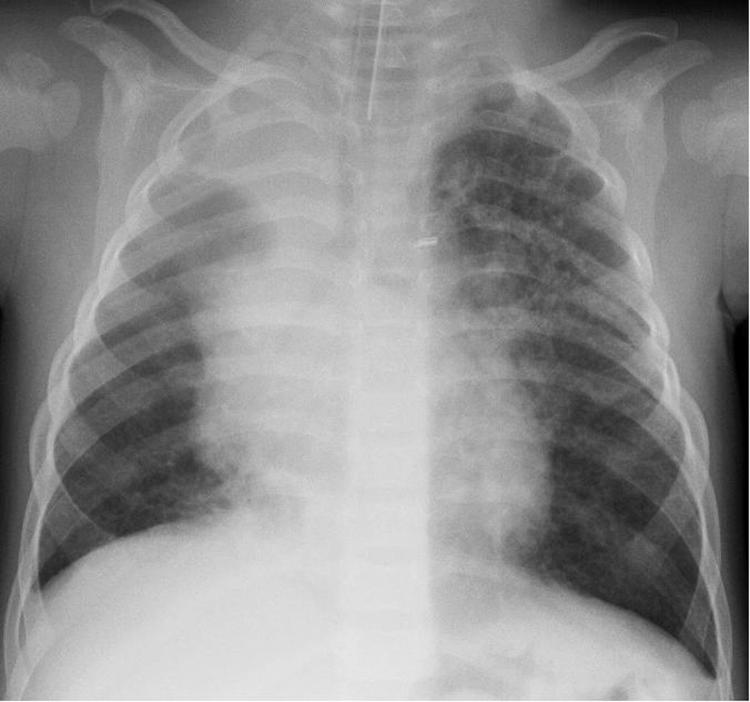

Human bocavirus 1 (HBoV1) was detected in a young child hospitalized for pneumonia and subsequently in his twin brother and other family members. The mother's nasopharyngeal samples intermittently showed HBoV1 DNA; the grandmother had HBoV1 reinfection. Findings in this family lead to consideration of HBoV virulence, latency, and reactivation.